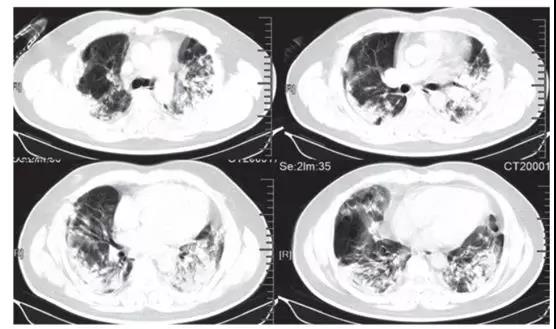

中国学者Lancet刊文称新型病毒感染有四大常见表现: 发烧、干咳、呼吸困难和双侧毛玻璃状样变!

2020-11-11